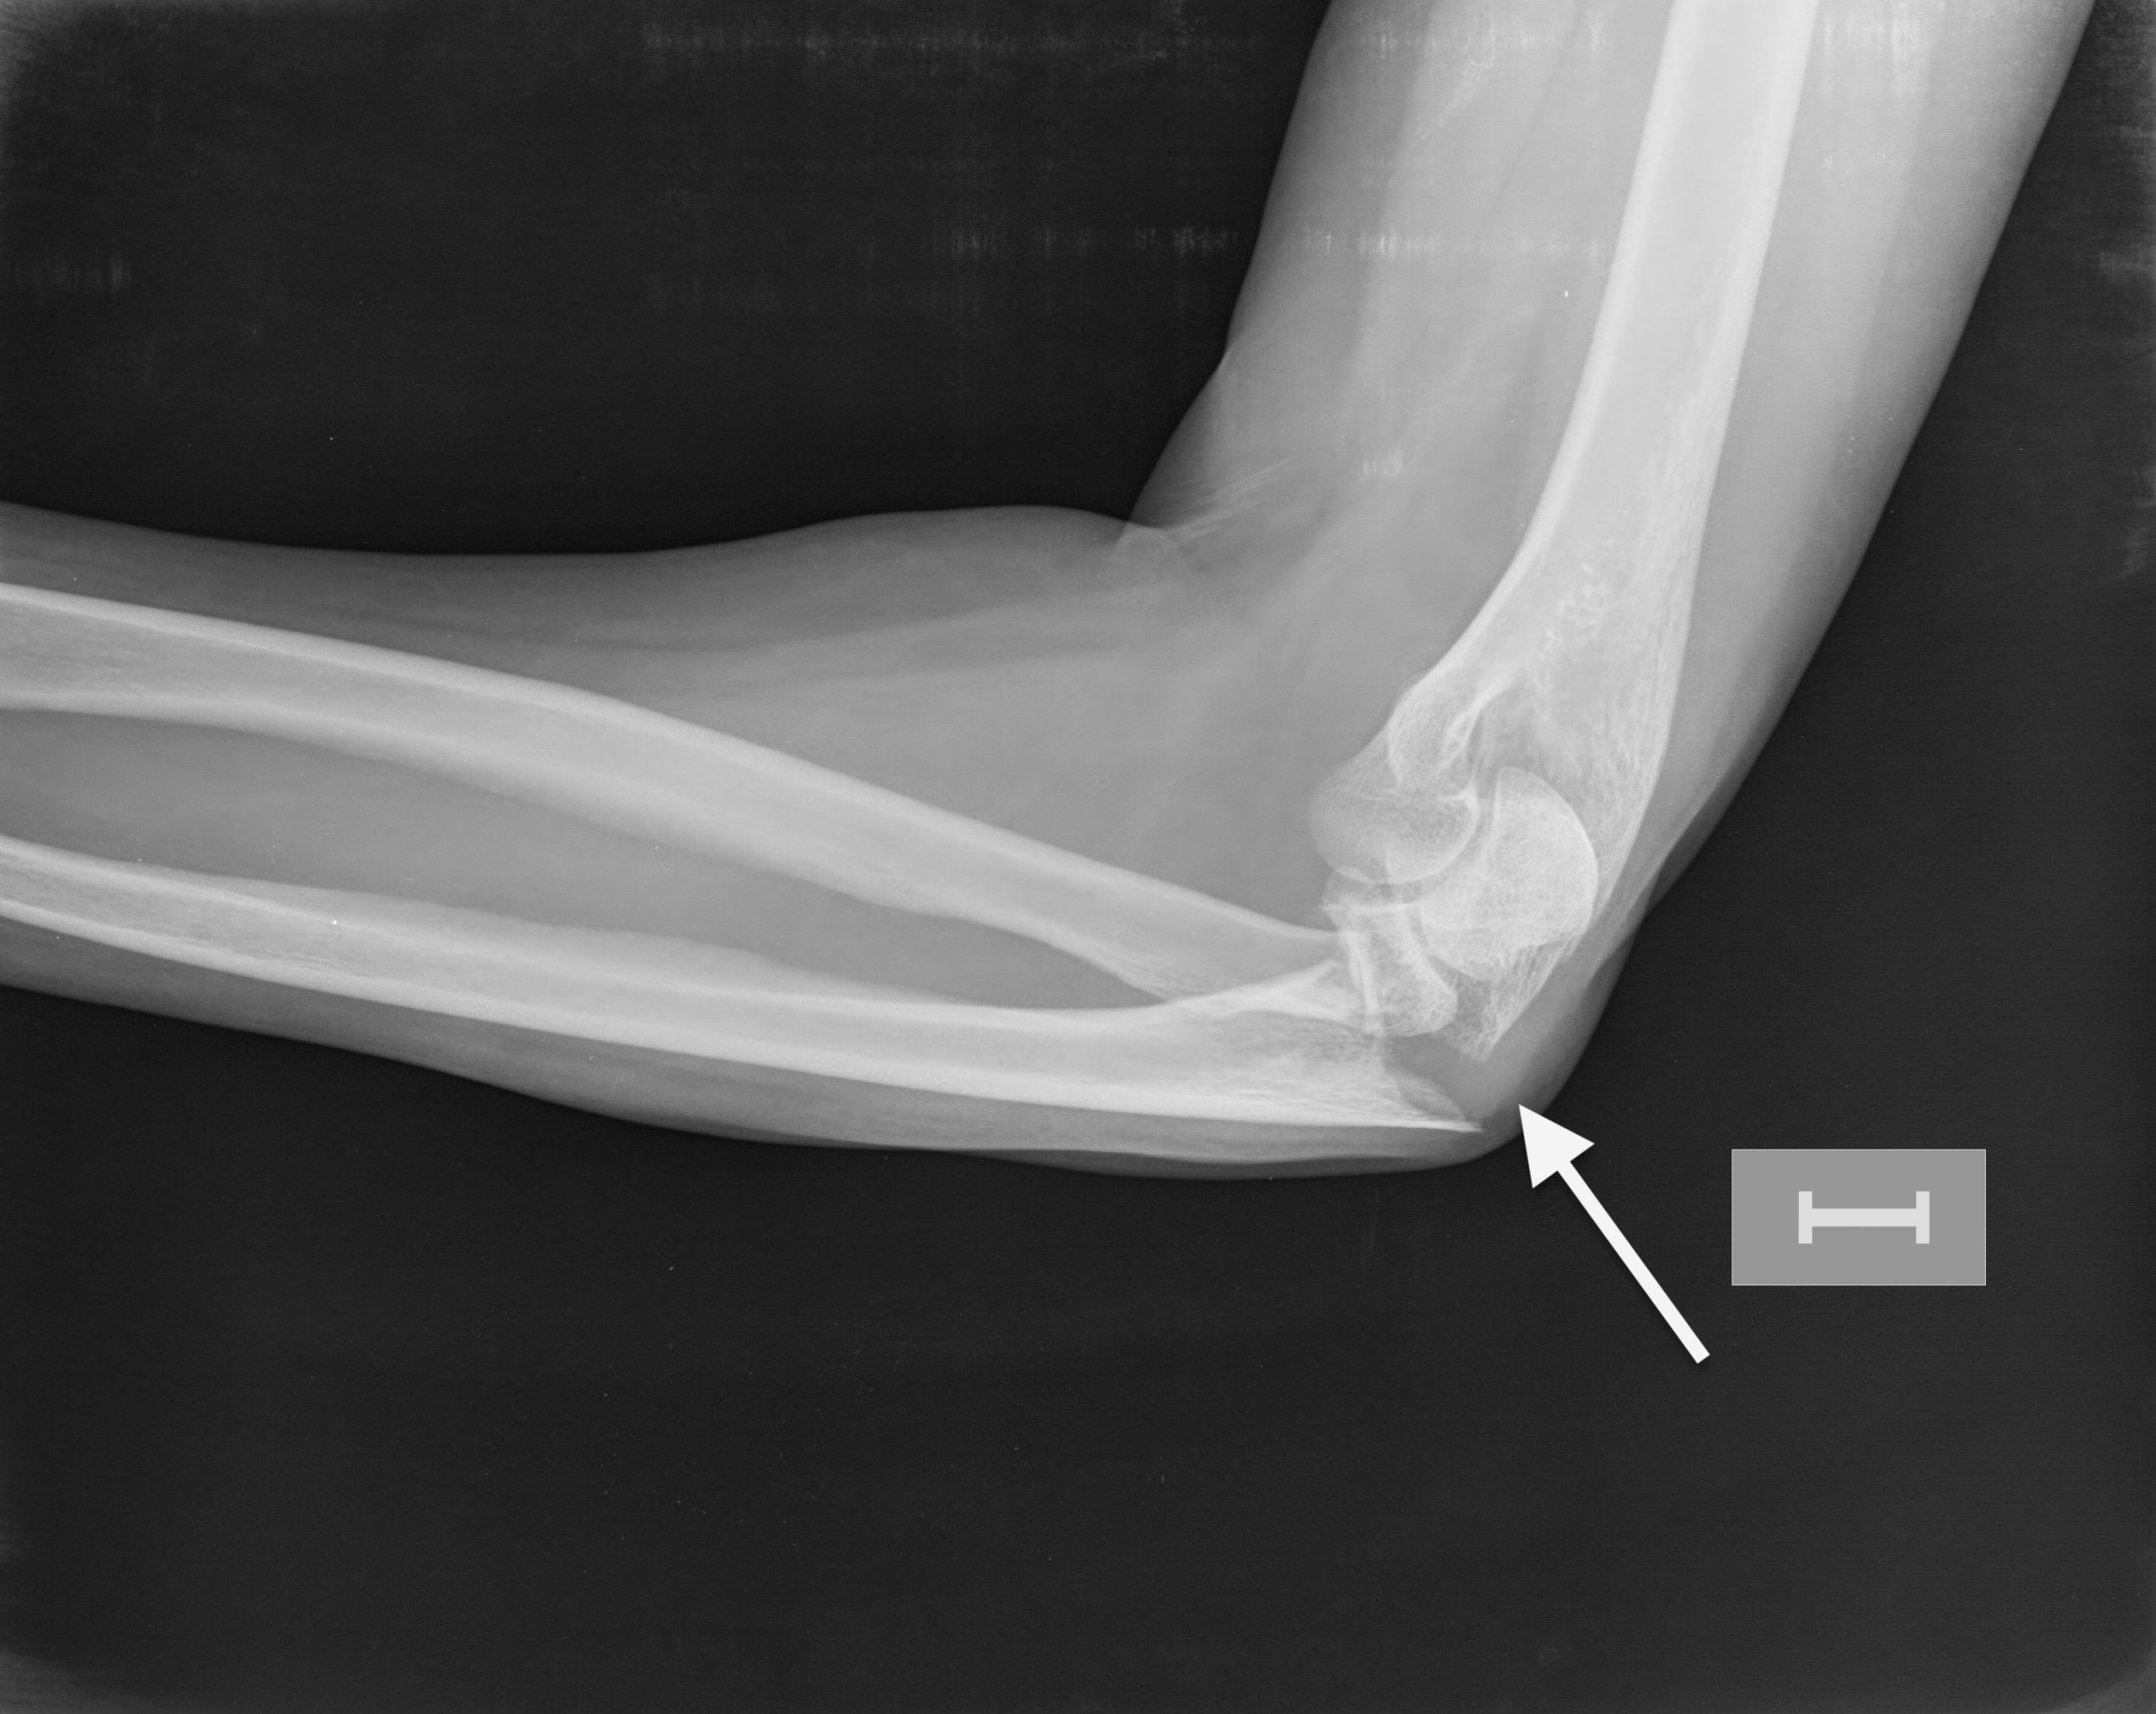

Fracturas de olécranon (Figura 2)

Estas fracturas, por lo general, están desplazadas y necesitan cirugía. Los fragmentos de los huesos se vuelven a alinear y se sintetizan con clavos y alambres o placas y tornillos.

Figura 2 - Fractura de olécranon y cúpula radial.